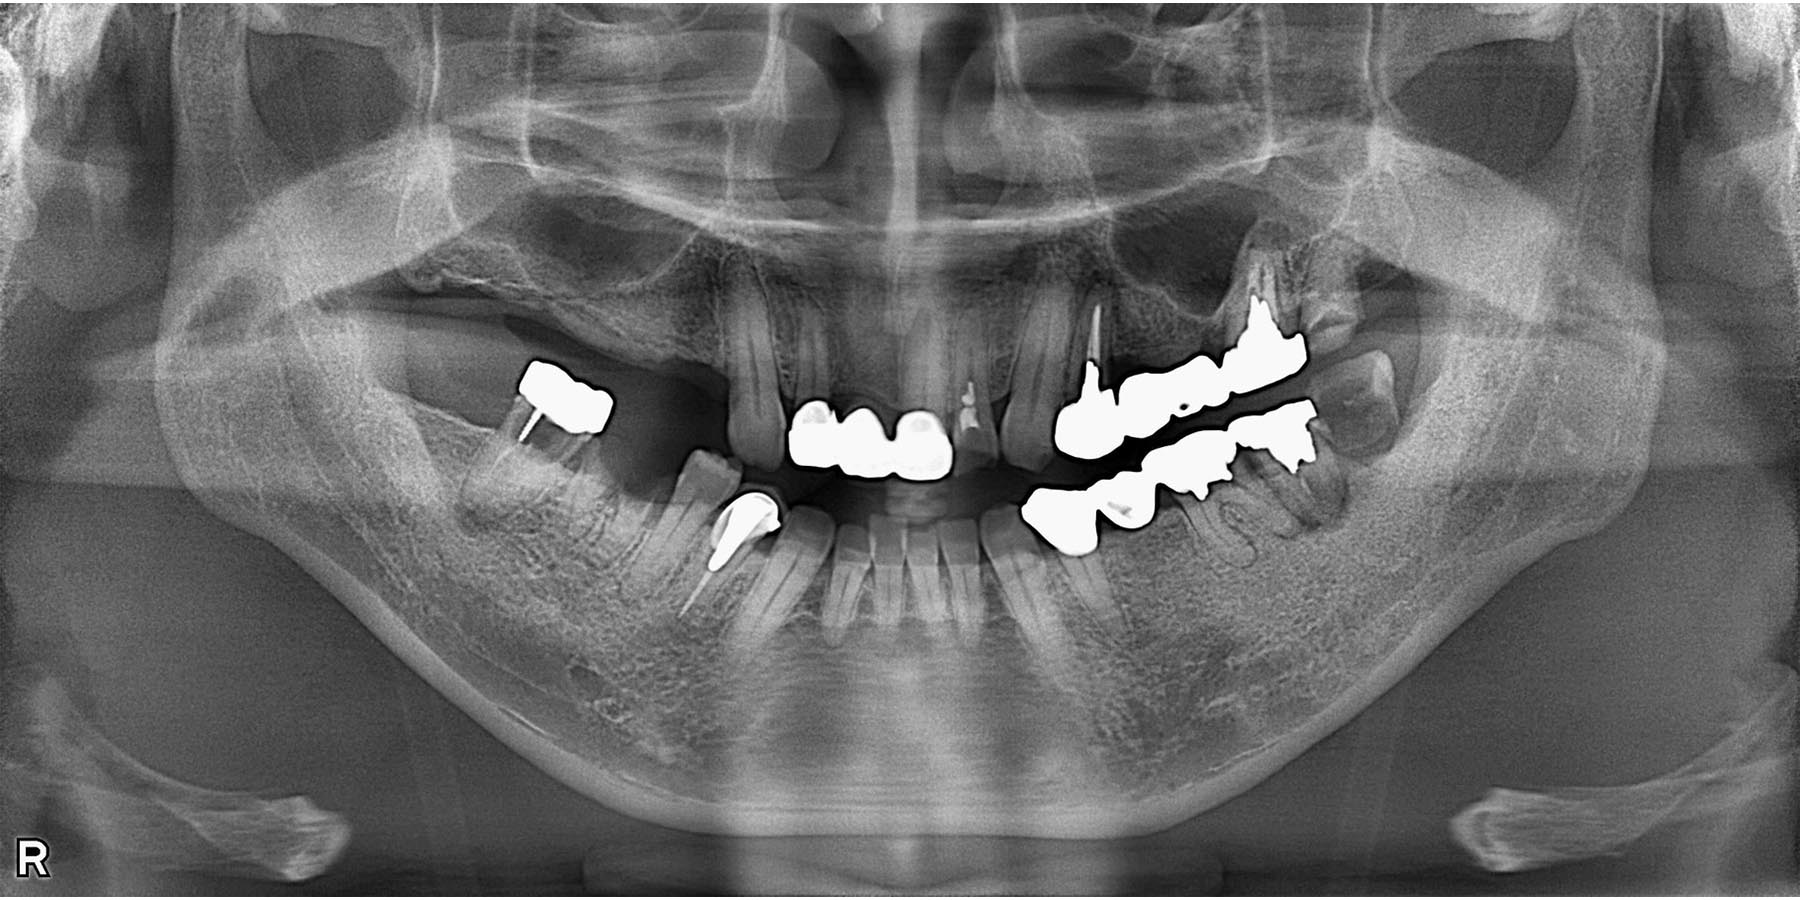

治療前